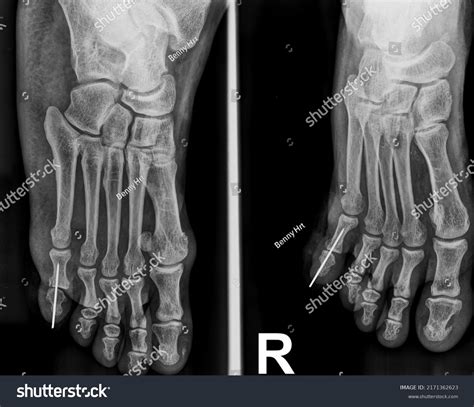

Okay, before we get into the nitty-gritty of ICD-10 codes, let’s quickly review the common foot bones and fracture types . The foot is a complex structure composed of 26 bones, divided into three main sections: the forefoot, midfoot, and hindfoot. The forefoot consists of the metatarsals and phalanges (toes), the midfoot includes the cuneiforms, navicular, and cuboid bones, and the hindfoot is made up of the talus and calcaneus (heel bone). Fractures in any of these bones can be quite painful and debilitating, affecting mobility and quality of life. Common types of foot fractures include metatarsal fractures, which are often seen in athletes or individuals who engage in high-impact activities. These fractures can occur due to direct trauma, overuse, or stress. Phalangeal fractures, or toe fractures, are also common and can result from stubbing the toe or dropping a heavy object on the foot. Midfoot fractures, such as those involving the navicular or cuneiform bones, are less frequent but can be more complex and may require surgical intervention.

Hindfoot fractures, particularly calcaneal fractures, are often caused by high-energy injuries like falls from a height or motor vehicle accidents. These fractures can be severe and may involve significant soft tissue damage. Another important type of foot fracture is a stress fracture, which is a small crack in the bone that develops over time due to repetitive stress or overuse. Stress fractures are commonly seen in runners, dancers, and military personnel. They typically occur in the metatarsals but can also affect other bones in the foot. When classifying foot fractures, it’s important to consider several factors, including the location of the fracture, the type of fracture (e.g., transverse, oblique, spiral, comminuted), and whether the fracture is open or closed. An open fracture, also known as a compound fracture, involves a break in the skin that exposes the bone to the outside environment, increasing the risk of infection. A closed fracture, on the other hand, does not involve a break in the skin. Additionally, fractures can be displaced, meaning the bone fragments are misaligned, or non-displaced, meaning the bone fragments are still in their normal alignment. Understanding these different types of foot fractures and the specific bones involved is crucial for accurate diagnosis and treatment planning. It also lays the groundwork for correctly assigning the appropriate ICD-10 codes, which we’ll delve into next.